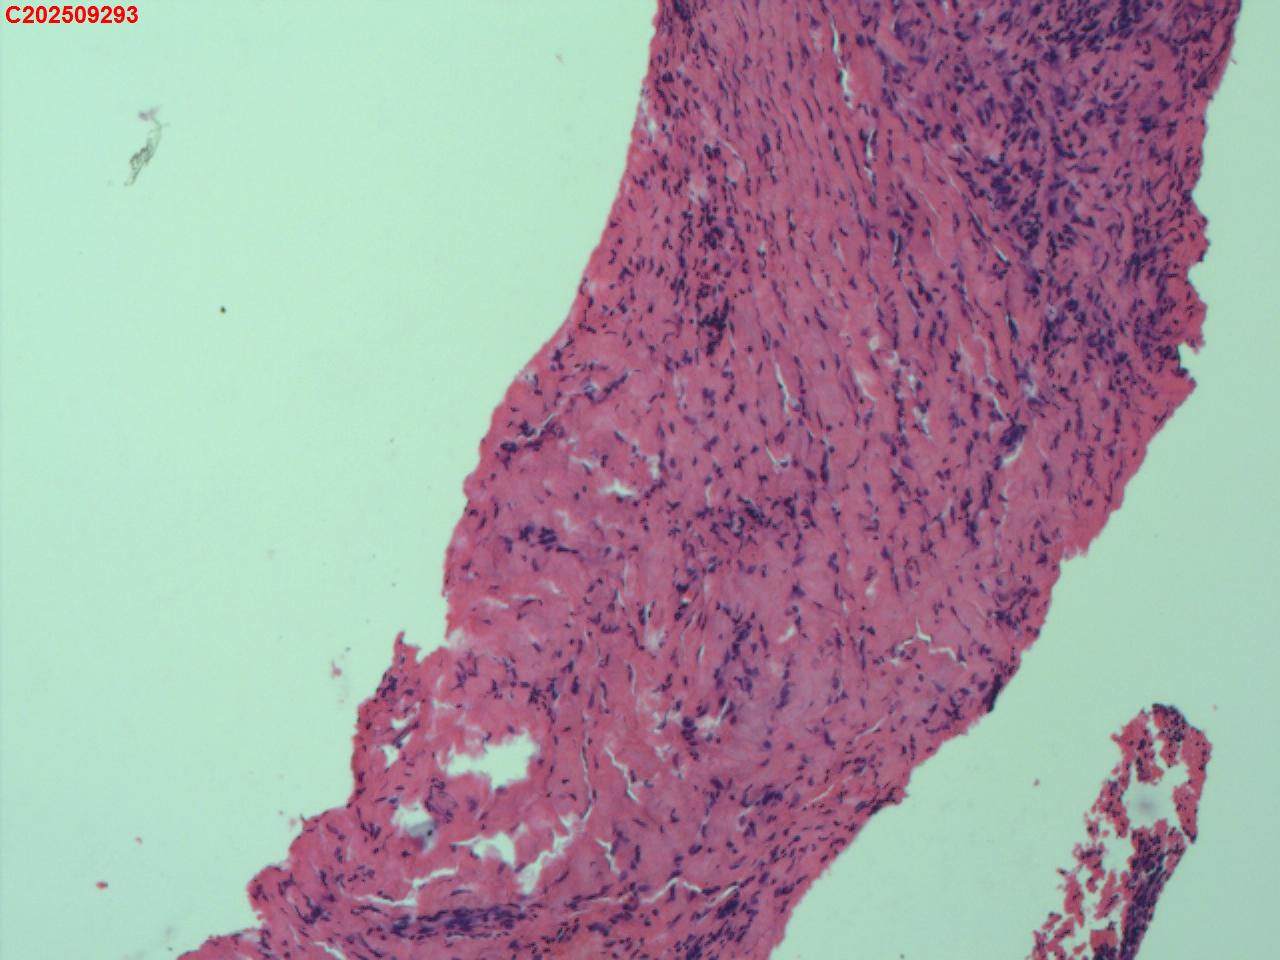

性别

女

年龄

34岁

临床诊断

胸膜结核瘤

一般病史

超声:可见右侧胸膜包裹囊性病变并见胸膜结核瘤。

标本名称

肺穿活检

大体所见

CT:胸部增强CT示右肺病灶局部增大,右侧胸腔结核性胸膜瘤可能。

送检组织·,镜下为炎性细胞和纤维组织。